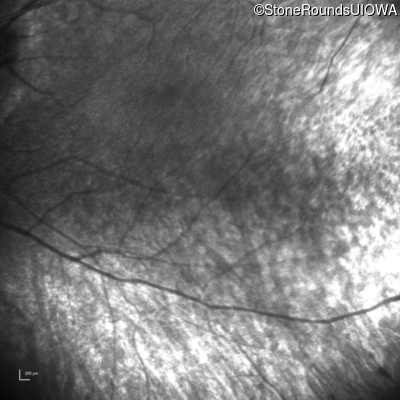

Infrared Fundus Photograph - Right - Light Perception

Exemplar